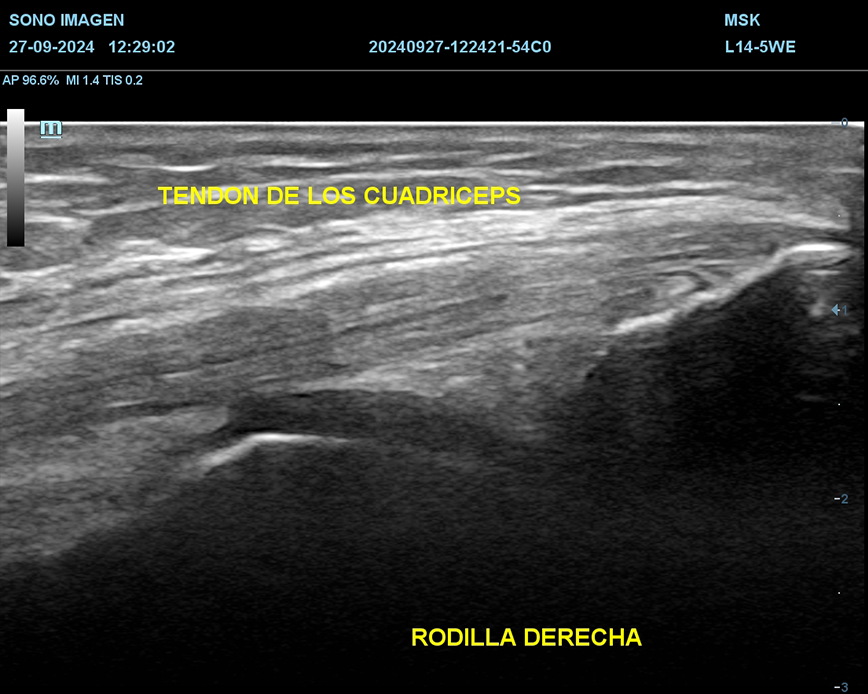

Ecografía de rodilla

- evaluación del dolor de rodilla

- lesiones de tejidos blandos: tendinosis, desgarros ligamentosos, rupturas meniscales.

- evaluación de lesiones deportivas

- traumatismos